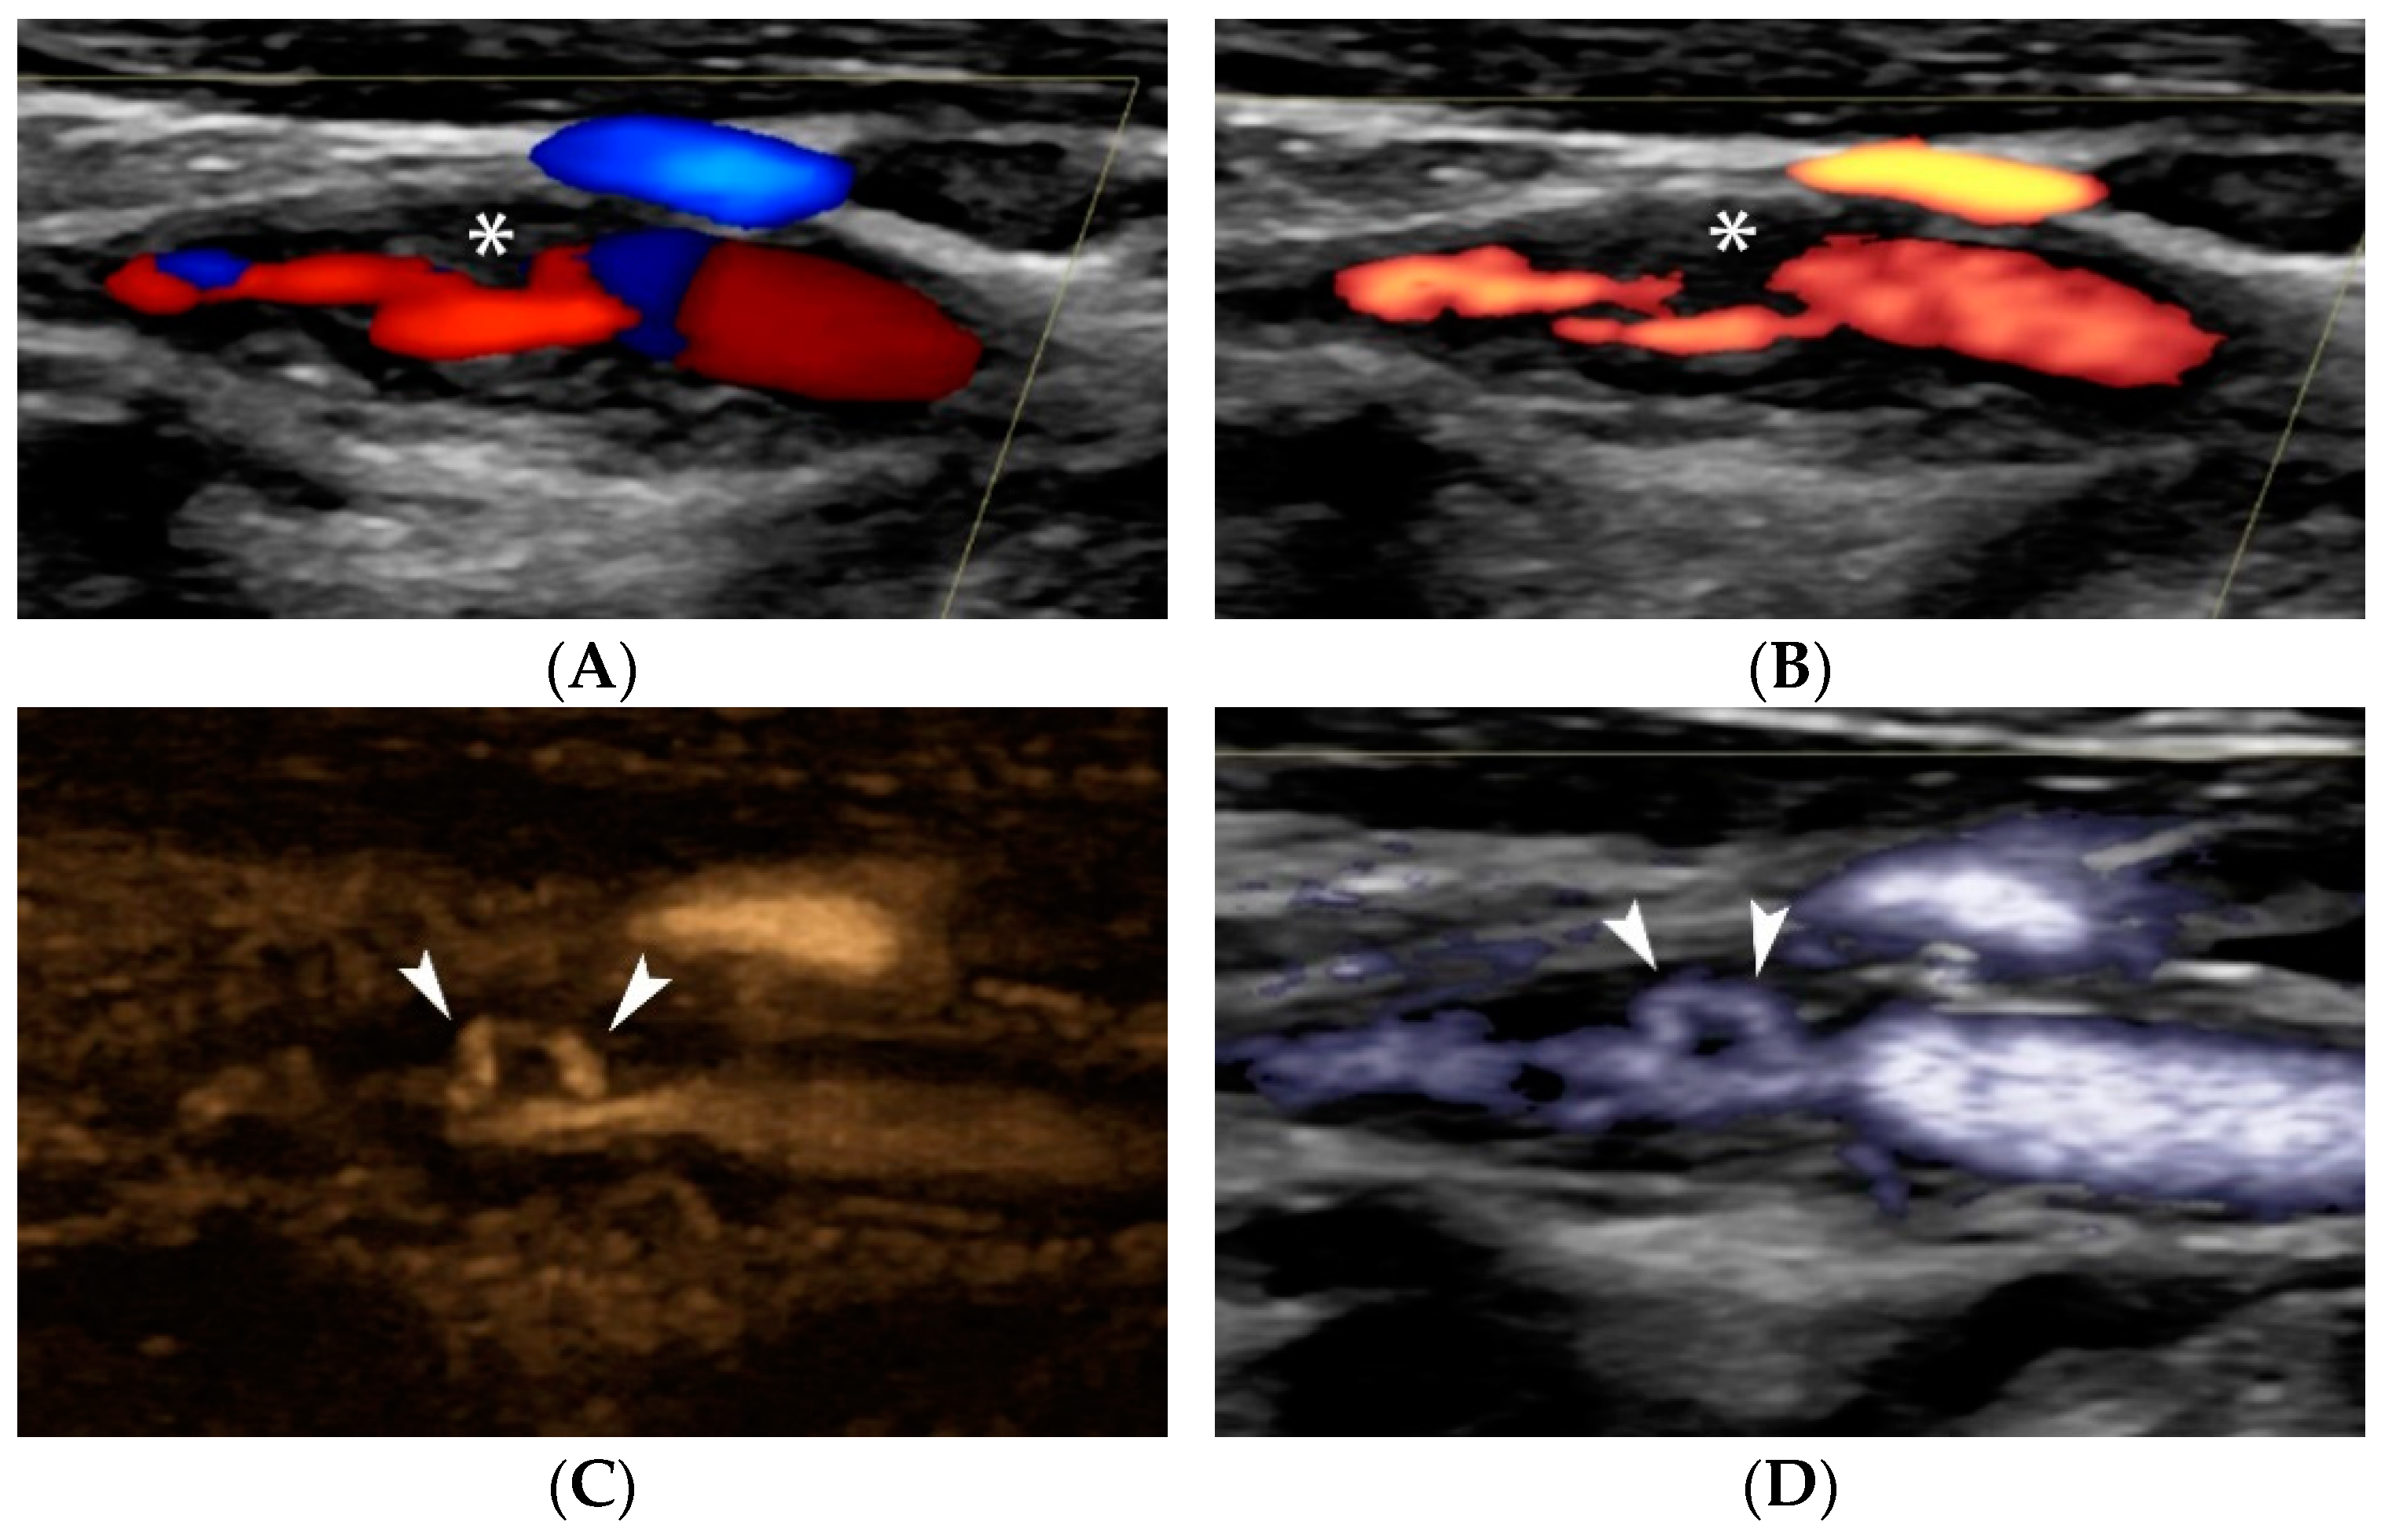

4. Contrast-Enhanced Ultrasound (CEUS)

4.1.1. Intraplaque Neovascularization

- Rafailidis, V.; Chryssogonidis, I.; Xerras, C.; Grisan, E.; Cheimariotis, G.A.; Tegos, T.; Rafailidis, D.; Sidhu, P.S.; Charitanti-Kouridou, A. An Ultrasonographic Multiparametric Carotid Plaque Risk Index Associated with Cerebrovascular Symptomatology: A Study Comparing Color Doppler Imaging and Contrast-Enhanced Ultrasonography. Am. J. Neuroradiol. 2019, 40, 1022–1028. [Google Scholar] [CrossRef] [PubMed]

- Rafailidis, V.; Chryssogonidis, I.; Xerras, C.; Nikolaou, I.; Tegos, T.; Kouskouras, K.; Rafailidis, D.; Charitanti-Kouridou, A. A comparative study of color Doppler imaging and contrast-enhanced ultrasound for the detection of ulceration in patients with carotid atherosclerotic disease. Eur. Radiol. 2019, 29, 2137–2145. [Google Scholar] [CrossRef]